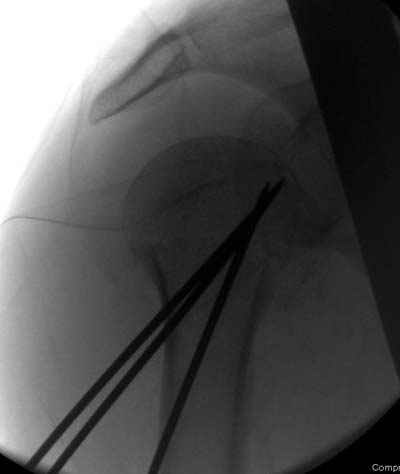

Идеей презентации случая была демонстрация важности постоп Рг - хотя казалось бы все было сделано под флюороскопическим контролем и интраоперационно подозрений на нестабильность не возникло, а такая вот

неожиданность...

Сегодня взял больного повторно в операционную, не скажу, что повторная репозиция через неделю после первой попытки, была простая.

После удаления спиц попытался манипулировать отломками, но безуспешно, поэтому пришлось пользоваться периостальным элеватором, чтобы устранить смещение отломков и перепровести спицы. Проверил и перепроверил стабильность фиксации под ЭОПом, завтра Рг- будет готов, вот и поглядим....

Посылаю послеоперационные Рг граммы.

Всего Доброго,

Поздравляю, получилось просто замечательно. Если можно, расскажи чуть подробнее, как делали - как вправляли, как вводили спицы, поворачивали ли их?

Я и сам доволен результатом. В предпоследнем письме я кратко описал ход операции - закрыто репонировать не удалось( 2 недели с момента травмы и 1 неделя после неудачной репозиции) после удаления пучков спиц, пришлось сделать - 2см разрез на уровне перелома и с помощью периостального элеватора (золотое правило механики) *одеть* головку на дистальный отломок.

Спицы проводил через старые отверстия, вращая пучок импактором- направителем при его введении в головку.